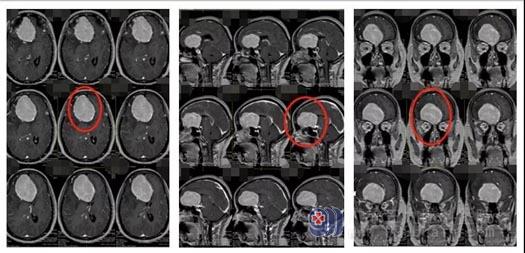

▲王大姐术前影像检查

▲王大姐术后影像检查

经过周密的术前讨论,与患者及家属沟通后,鲁明团队决定先为患者实施供血供血血管部分栓塞术,再进行前颅底巨大脑膜瘤切除术。由于术前准备充分,鲁明完整地将一个7cmx5cm大的肿瘤切除了。这个手术在疫情期间确实来之不易,但手术圆满成功。术后再次进行新冠肺炎筛查,仍为阴性,目前患者恢复良好。